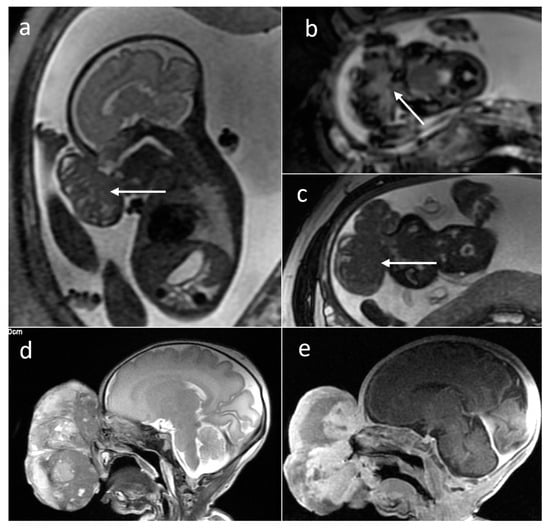

| Rhabdomyoma | heart | 22 | 5.08 [0.1–22] | no | Solid | No | N/A |

| Subependymal giant cell astrocytoma | foramen of Monro | 6 | 0.74 [0.59–0.89] | no | Solid | yes (2/2) | N/A |